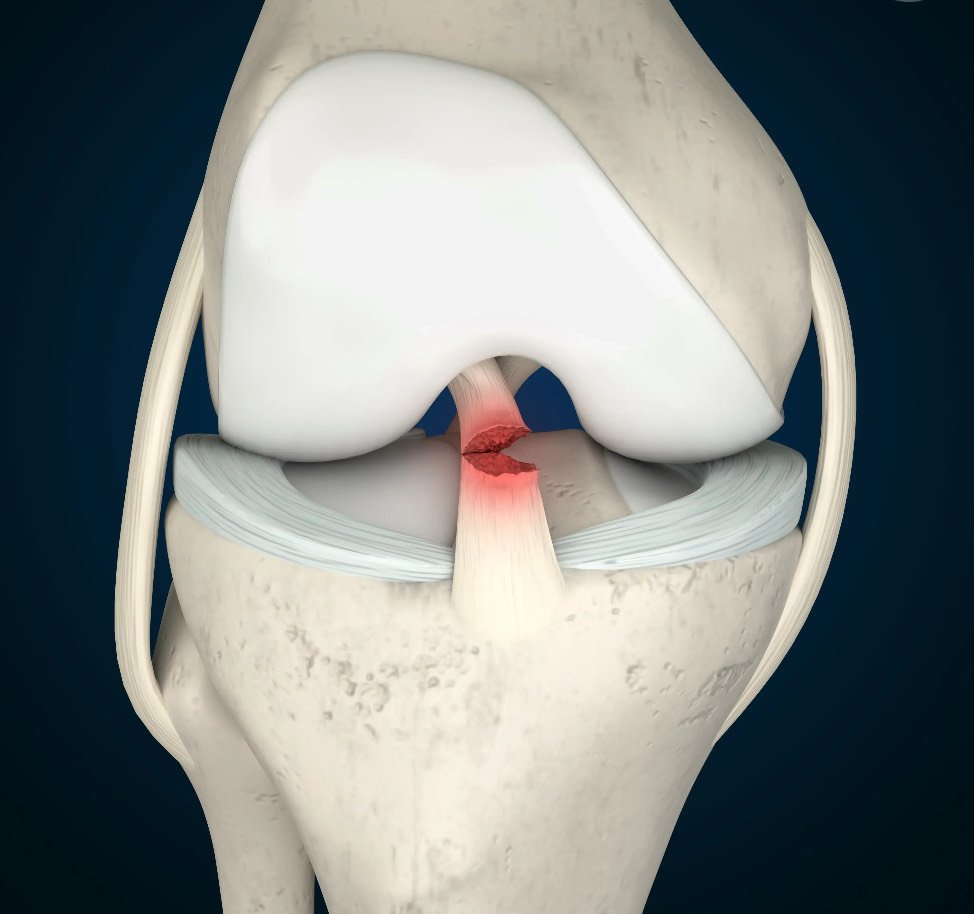

The anterior cruciate ligament (ACL) is one of the key ligaments that helps stabilise your knee joint. It connects the thigh bone (femur) to the shin bone (tibia) and plays an important role in controlling forward movement and rotation of the knee. An ACL tear is a common injury, especially among athletes and physically active individuals. It can occur during sudden stops, pivots, changes in direction, or direct impacts to the knee.

- MRI scan: The most accurate way to confirm a complete or partial tear and assess other internal knee injuries such as meniscal tears or bone bruising